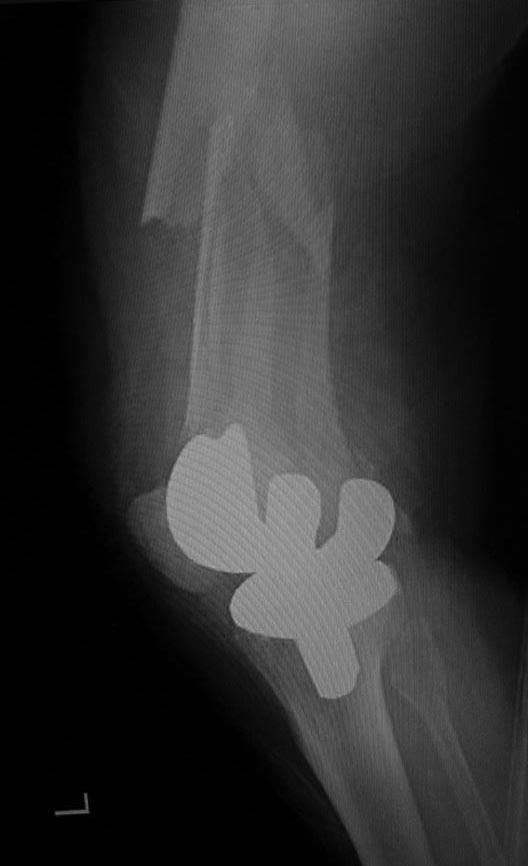

[Ortho] Перипротезный перелом дистального отдела бедра

Что можно сделать? Бедренный комплект бесцементный

Имя     : lat.jpg